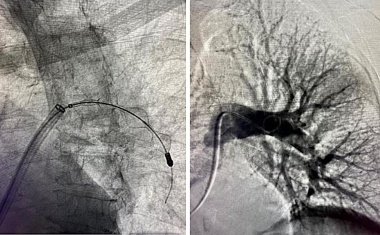

Neues innovatives System erstmals zur Behandlung von Lungenembolien am Universitätsklinikum Freiburg eingesetzt